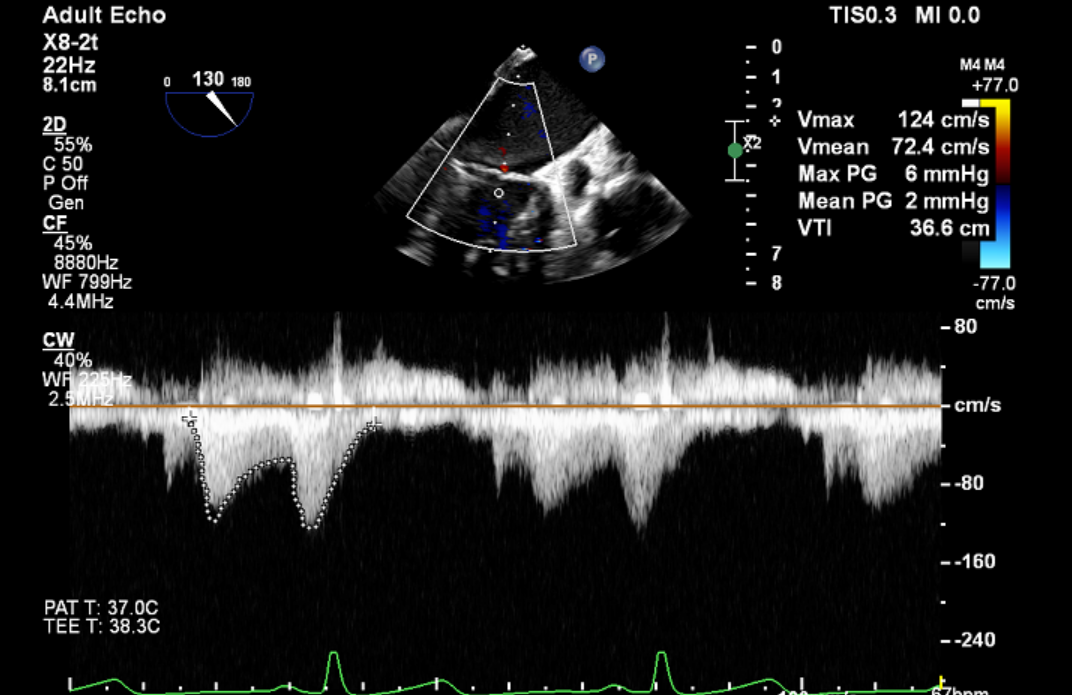

将MitraClip™XTR送入左房,由于左房太小,在达到骑跨过程中反复推进回撤CDS和稳定器,同时旋转SGC,达到骑跨的同时,保证Clip头端游离,且SGC在左房有深度。旋转M,同时顺时针往后旋转SGC借高度,使Clip垂直二尖瓣环平面,由于穿刺高度不够,Clip直接进入左室,这意味着操作要十分小心,左室组织复杂,稍有不慎将会造成组织损伤。使用A/P Konb中“A”旋钮借高度。确认垂直后,直接在左室打开Clip,3D外科视角,逆时针旋转使Clip夹臂处于11点-5点方向,回拉稳定器,使Clip处于3区脱垂区域,用“+/-”Knob中的“-”旋钮,使Clip更往后叶的同时增加操作高度,抓捕脱垂的瓣叶,关紧Clip后,反流从4+降低至0级,平均跨瓣压差2mmHg,左右肺静脉逆流均改善。前后叶活动度降低,后叶插入长度9mm,前叶插入12mm, 确认稳定性后释放Clip。释放后,即刻效果十分满意,手术圆满结束。